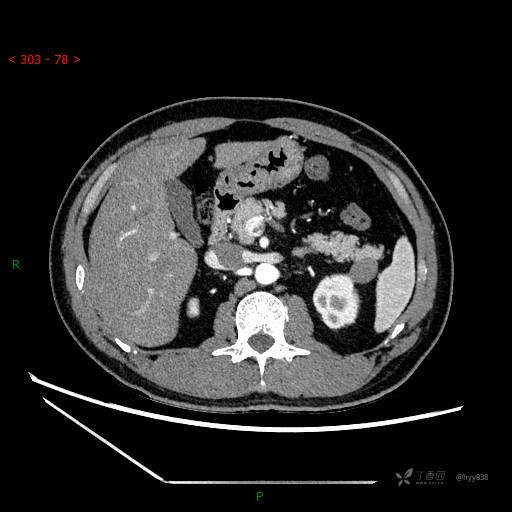

MRI(T1WI+T2WI-fs+DWI+ADC)